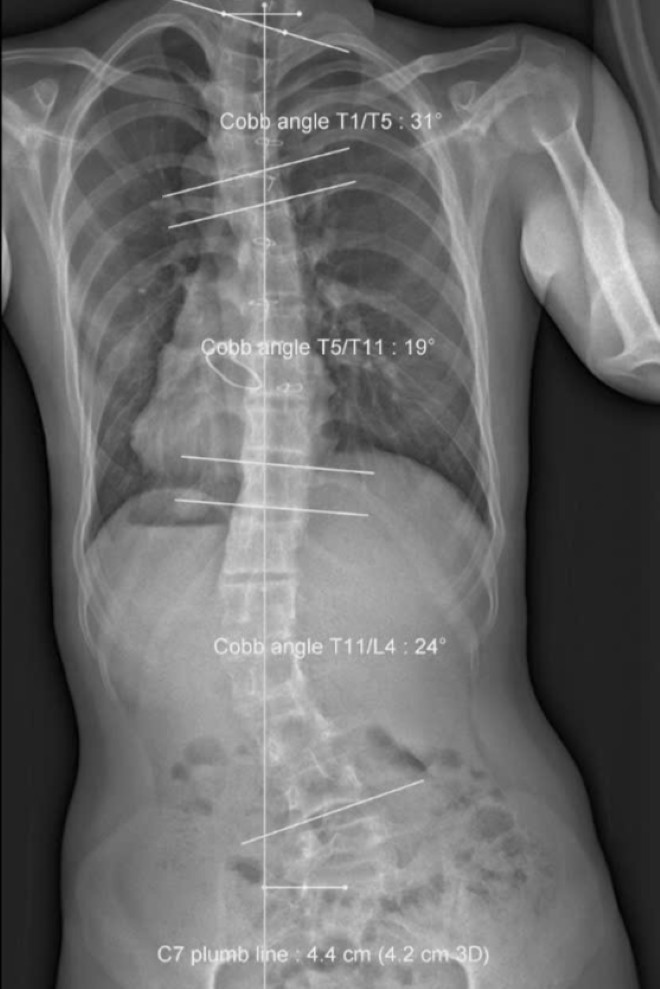

At the HMR Center, X-ray results showed severe deformities, including misalignment of all ankle and knee joints, a tilted and rotated pelvis, and an S-shaped spinal curvature exceeding 40 degrees.

After 20 therapy sessions, the patient’s pelvis had significantly improved, showing reduced leftward tilt. By the 40th session, his pelvis was fully aligned, and his spinal curvature had improved by nearly 20 degrees, restoring his body to a straighter axis.